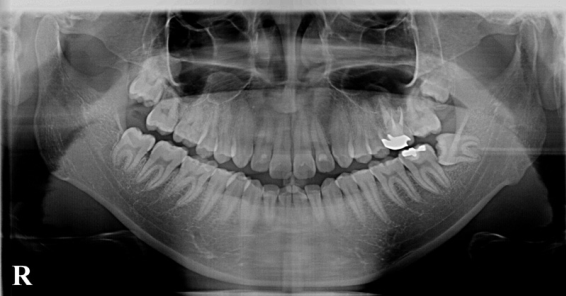

被曝量の少ないデジタルレントゲンをはじめ、針の細い電動注射器など、様々な機器を活用して、患者様の身体に負担をかけず痛くない治療を目指しております。

初めて来院頂きましたら、まずはレントゲン撮影を行うことがほとんどです。

当院では通常の2分の1以下という低線量での撮影が可能なデジタルレントゲンを使用しております。

当院では、デジタルレントゲン、拡大鏡、口腔内カメラなどを活用しております。